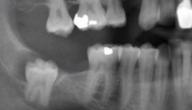

يكون ضرس العقل الضرس الثالث في آخر الفم، وقد لا تكون له مساحة كافية في الفم بعض الأحيان للنموّ طبيعيًّا، ويُعدّ من الأسنان الأخيرة التي تظهر في فم البالغين، إذ يظهر في الفترة العمرية ما بين 17 و25 عامًا، ويحتوي فكّ معظم الأشخاص البالغين على أربعة من ضروس العقل، اثنين منهما في الجزء العلوي، والآخرين في الجزء السفلي، ويرافق ظهور ضروس العقل ألم وأضرار قد تلحق بالأسنان الأخرى في الفم مع عدد من مشكلات الأسنان، وفي بعض الأحيان قد لا يُسبّب ظهورها أيّ مشكلات فوريّة، ونظرًا لصعوبة تنظيفها فإنّها تُكون أكثر عرضةً للتسوّس وأمراض اللثة مقارنةً بغيرها من الأسنان، لذلك يوصي معظم الأطباء بإزالتها لمنع ظهور أيّ من المضاعفات المرتبطة بها[١].

• تسوس الأسنان، يُعدّ ضرس العقل أكثر عرضةً للتسوس من غيره من الأسنان، ونظرًا لصعوبة تنظيفه فقد يعلق الطعام والبكتيريا بين اللثة والأسنان مسببًا التسوس.

• تضرر الأسنان المحيطة، يُسبّب احتكاك ضرس العقل بالأسنان المجاورة الضرر، كما أنّه يؤدّي إلى ازدحام الفم نتيجةً لدفع الأسنان الأخرى القريبة منه مُسببًا العديد من المشكلات لها، وقد تحتاج إلى العلاج بالتقويم لاستعادة استقامتها وإعادتها إلى شكلها الصحيح.

• الخراجات، وهي من المضاعفات النادرة، لكنّها تُعدّ خطيرةً، وتنتج عن نموّ كيس مليء بالسوائل، وقد يتسبّب في الضرر لعظام الفك والأسنان والأعصاب، وفي حالات نادرة قد يتطوّر إلى ورم حميد يتطلّب إزالة الأنسجة والعظام.